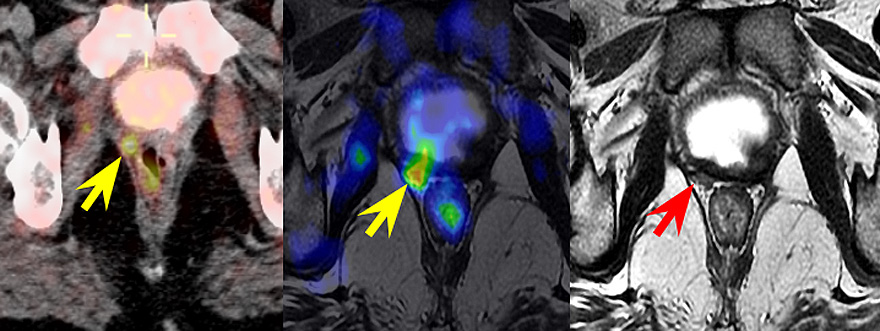

La investigación ha observado que la resonancia magnética es más útil en la detección de recidivas locales. Ambas técnicas (PET-Colina y resonancia magnética) tienen una efectividad similar en la detección de afección linfática y metástasis óseas.

El uso de técnicas de imagen para la localización de las recidivas en el cáncer de próstata cambió en un 58 por ciento la decisión de tratamiento. La combinación de ambas técnicas permite realizar el tratamiento más adecuado para cada paciente.